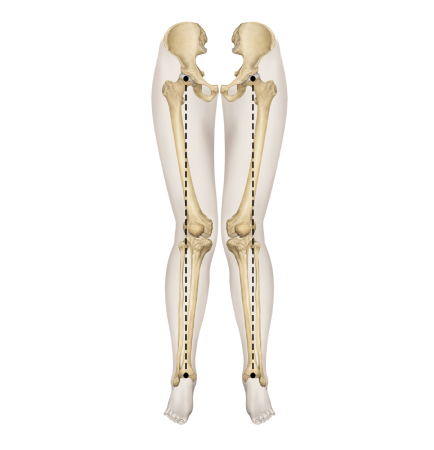

▲ O자 다리

휜다리의 대표적 유형 2가지

O다리

• 무릎이 외측으로 벌어지면서 다리 축이 변형됨

• 체중부하가 다리 안쪽(내측)에 집중되어 내측 관절의 압력증가로

무릎관절의 퇴행성 변화와 통증을 초래

• 허벅지 안쪽 근육이나 엉덩이 근육이 약화되면 무릎 안정성이 떨어져 내반슬이 악화

휜다리는 단순히 무릎 사이 간격이 벌어진 것이 아닙니다.

무릎 위의 대퇴골과 아래의 정강이뼈가 회전하면서 무릎까지 뒤로 빠지기 때문에 다리사이 간격이 넓어지는 겁니다.

발(아치)-발목-무릎관절-고관절-골반의 서로 다른 회전을 바로 잡는 기술입니다.

서양인들은 대부분 엑스다리인데 반해

한국과 일본인들은 대부분 좌식생활을 하고 양반다리 자세를 많이 해왔기 때문에

오다리 변형이 대부분입니다.

바닥에 앉을 때 고관절, 무릎관절이 접혀서 관절주변의 인대가 늘어난 상태로

체중이 가해지면 고관절이 회전하여

휜다리 변형이 유발

됩니다.